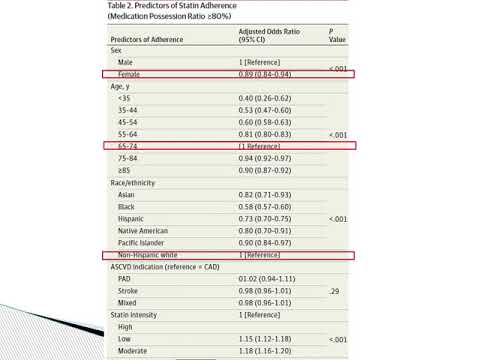

Asociación entre adherencia a estatinas y mortalidad en pacientes con enfermedad cardiovascular. Dr. Julián Colla. Residencia de Cardiología. Hospital C. Argerich. Buenos Aires